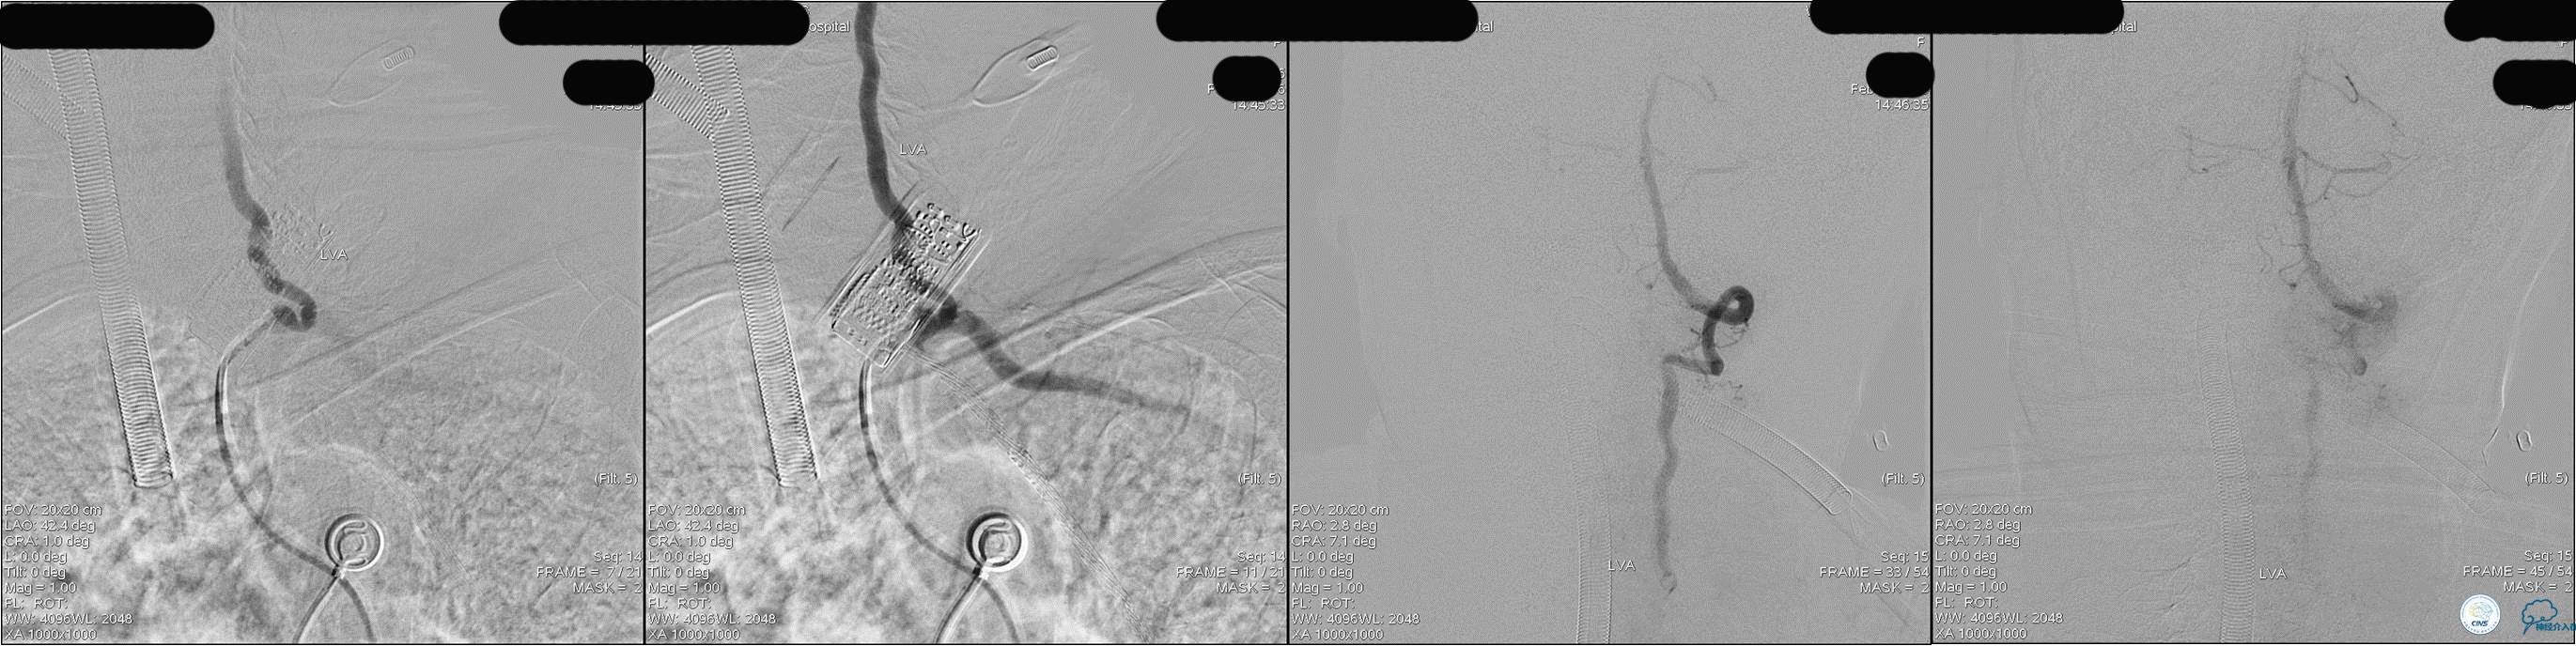

发病5.5小时给予股动脉穿刺

发现股动脉入路很差,考虑经桡穿刺。

》DSA资料(经桡动脉,5F导引导管)

》DSA资料(前2次取栓,未取出,soli 4-20)

》DSA资料(第3次取栓)

第3次取出血栓